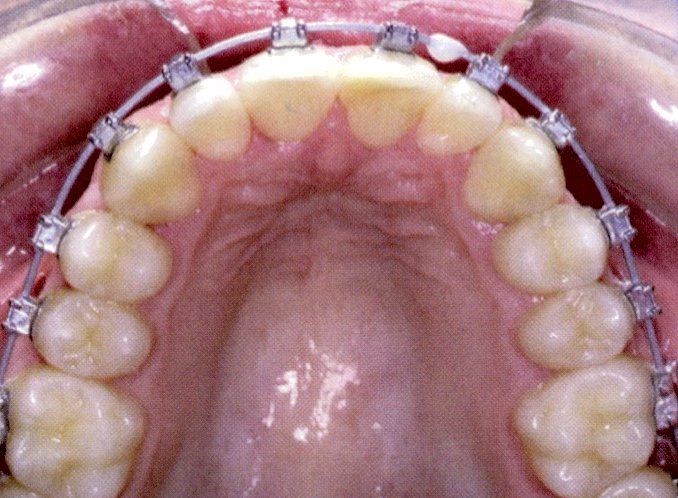

Ortodonzia dell'adulto

L'ortodonzia dell'adulto è solo ortodontica pura con solo spostamento dei denti, con sistema multi braket estetico trasparente oppure ortodonzia linguale, oppure con mascherine trasparenti (invisalign)